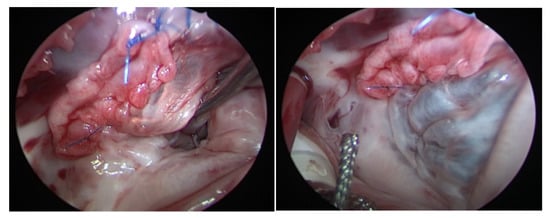

Figure 3.

(Right) TV after reconstruction and augmentation of the leaflets, the black arrow is pointing to the pericardial patch used to perform the augmentation. (Left) TV after injecting water in the RV for the water probe showing a competent TV. RV: right ventricle, TV: tricuspid valve.